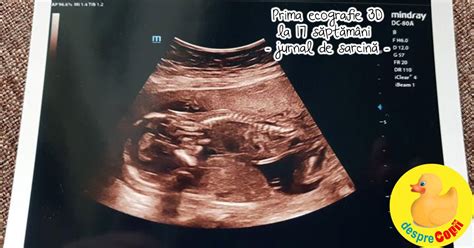

Un moment special al acestui trimestru este ecografia morfologică, de obicei efectuată între săptămânile 18 și 22. Aceasta este una dintre cele mai detaliate ecografii și are rolul de a verifica anatomia bebelușului, pentru a depista eventuale malformații. Poți vedea clar bebelușul pe ecran, iar medicul va putea să îți ofere informații despre dezvoltarea organelor, creierului, inimii, rinichilor și a altor structuri importante.

Între săptămânile 18 și 20 de sarcină vei face cea de a doua ecografie care are ca principal scop depistarea malformațiilor la copil (morfologia de trimestru 2). În plus, această investigație va permite să se aprecieze cât de exact s-a estimat data probabilă a nașterii, va evidenția dacă sarcina este multiplă, va localiza placenta și va verifica cordonul ombilical, identificând posibilele complicații.

În timpul examinării ai putea să vezi cum se mișcă copilul sau cum își suge degetul. În plus, cu această ocazie poți afla dacă este băiat sau fată, dacă vei dori acest lucru. Totuși, factori cum ar fi vârsta sarcinii sau poziția fătului pot influența acuratețea acestei afirmații. Ca să fii 100% sigură, va trebui să aștepți până vei naște! Ia-l cu tine și pe partenerul tău pentru a împărți aceste momente unice și cere-i medicului să îți dea o copie a acestor imagini care vor fi primele fotografii din albumul copilului tău.